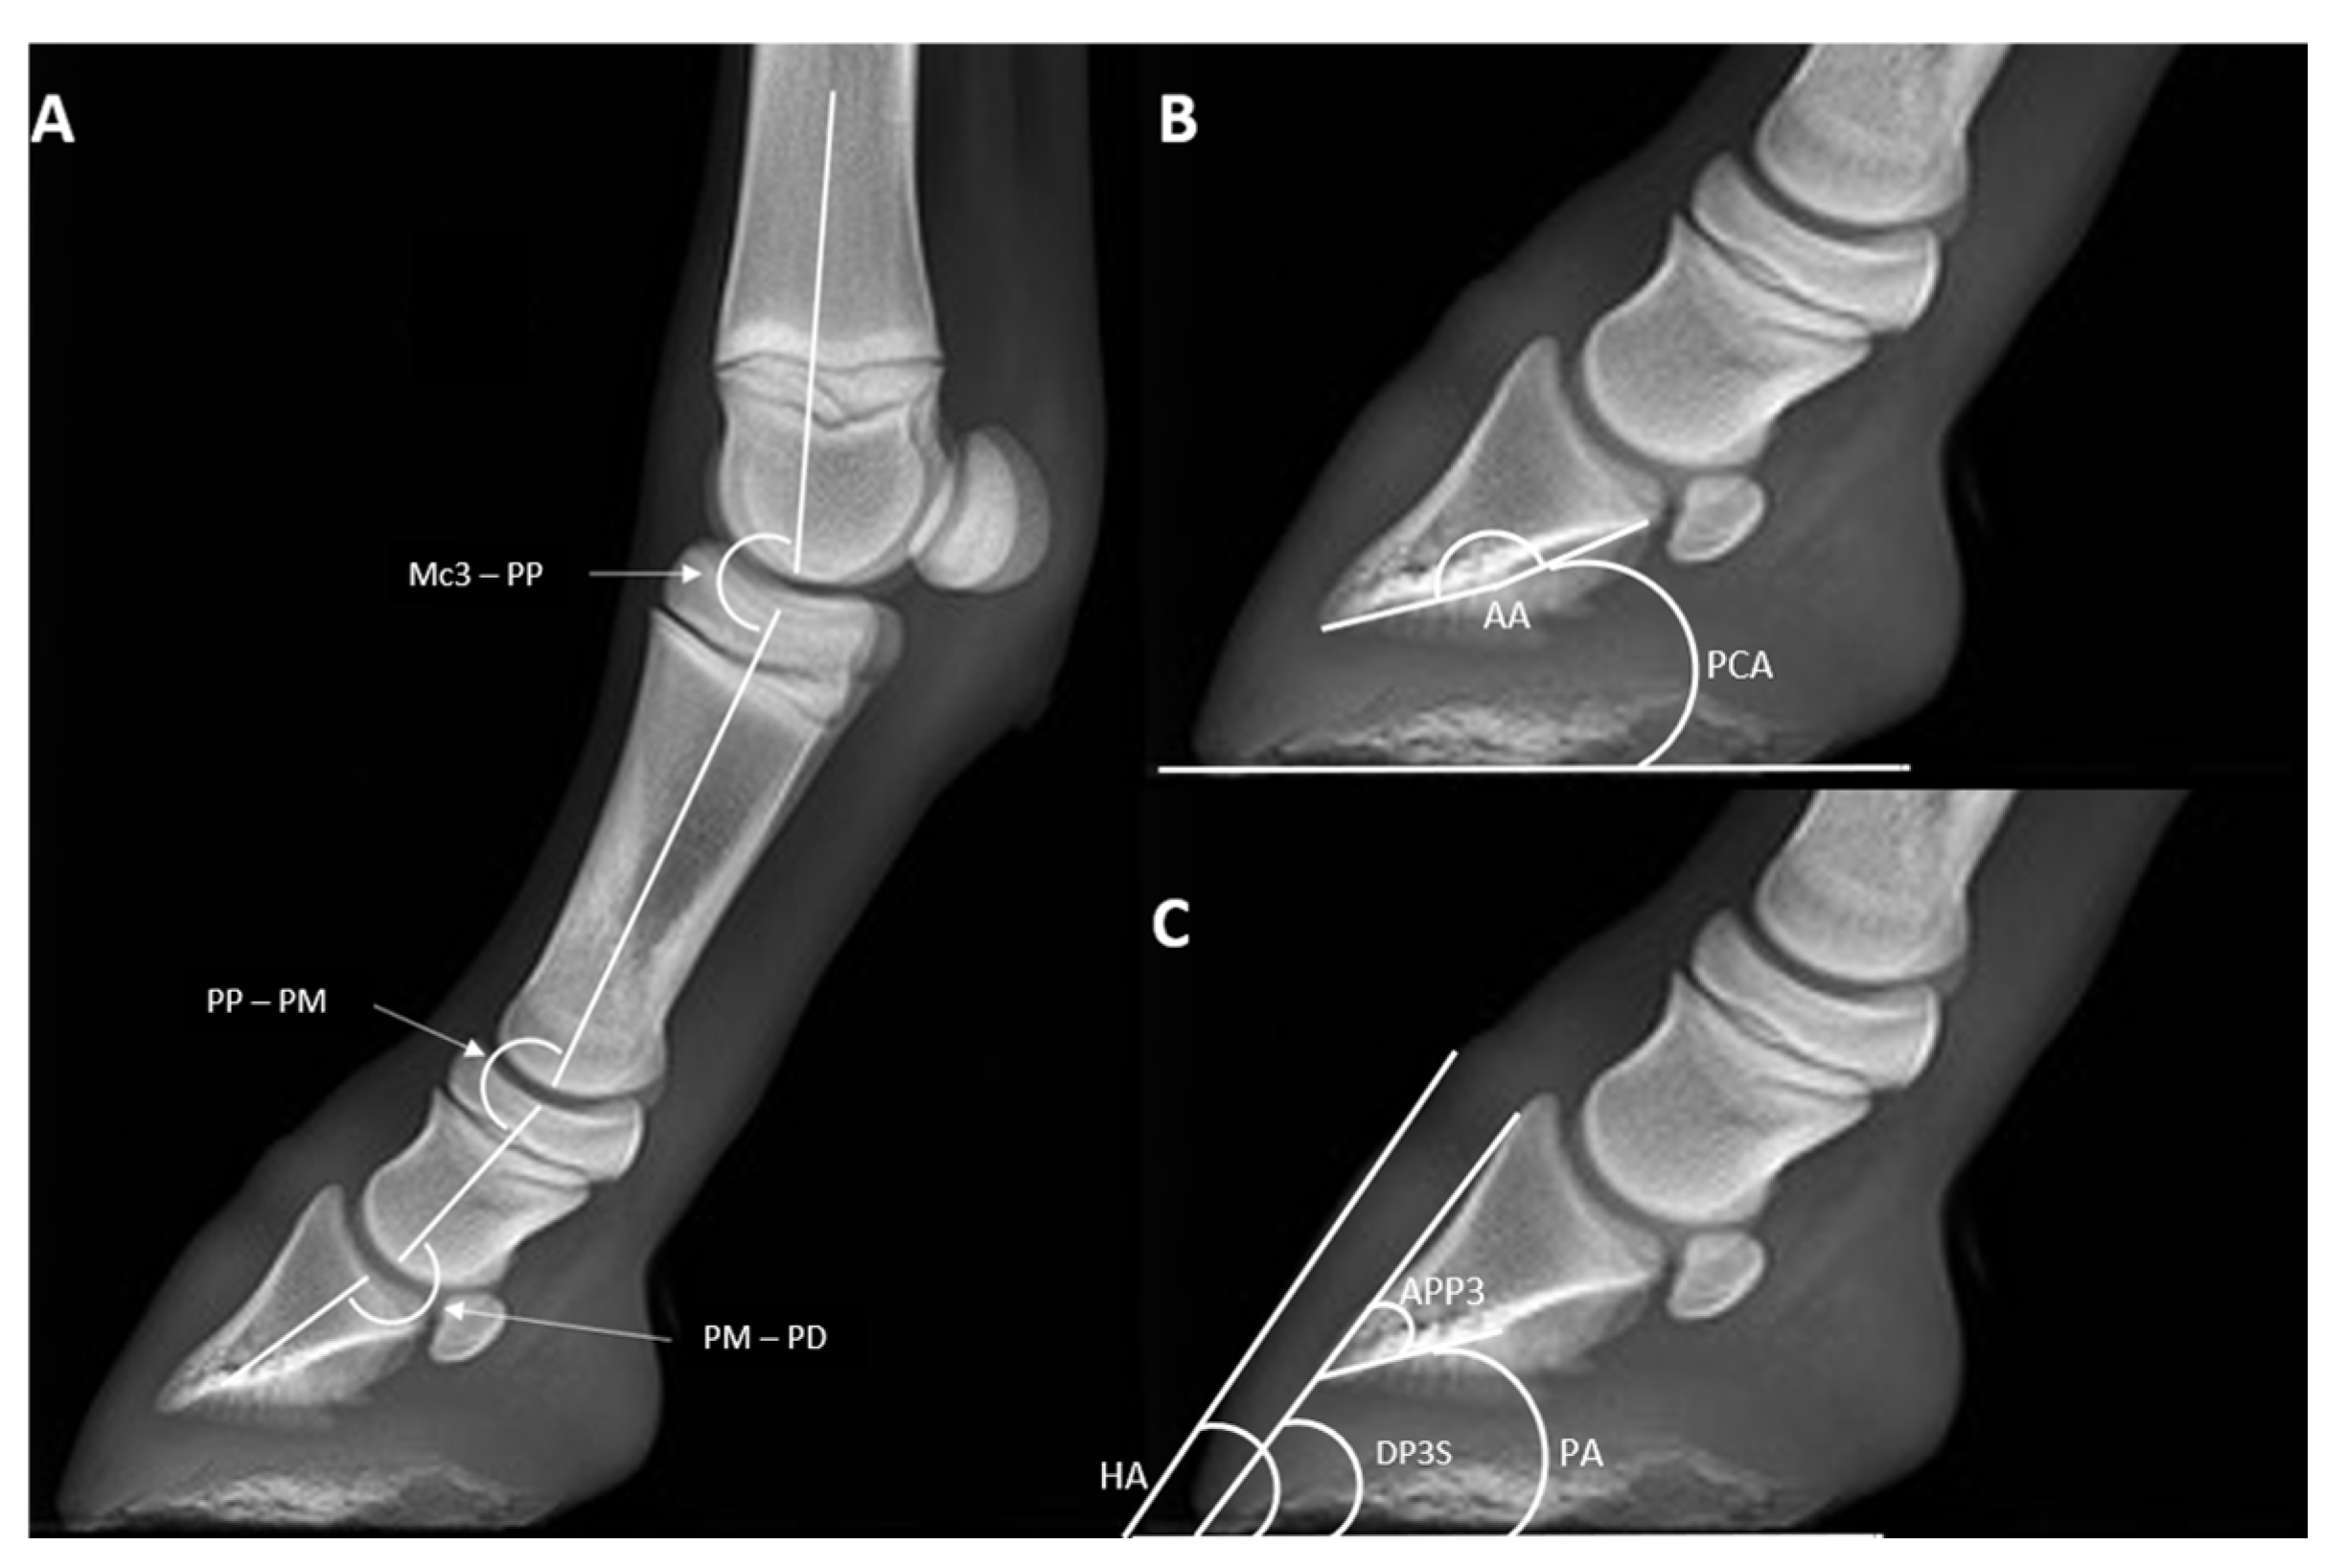

2.3. Radiological Parameters